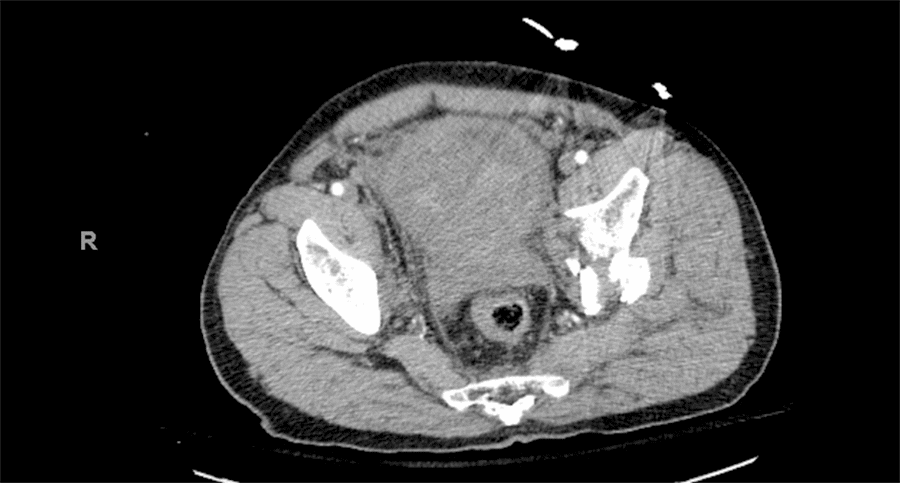

After initial resuscitation and subsequent stabilization, the patient was taken for a CT scan. Head and cervical spine imaging revealed no abnormalities. CT of the chest, abdomen, and pelvis revealed bilateral pneumothoraces, left 3-4 rib fractures, possible grade I splenic injury, lateral compression type 2 pelvic fracture with a left acetabular fracture, free intraabdominal fluid, and suggestion of intra/extraperitoneal bladder injury as well as a prostate injury with bony pelvic fragments protruding into the inferior bladder. There was a loss of delineation between the posterior aspect of the bladder and the prostate on CT imaging (Figure 1).

Figure 1. Cross-Sectional CT Imaging Demonstrating Loss of Delineation between Posterior Aspect of Bladder and Anterior Prostate. Published with Permission

Scattered heterogeneous debris noted within the urinary bladder